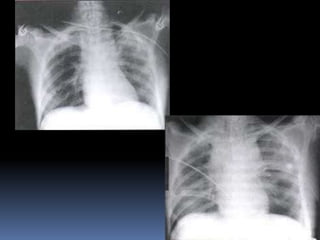

CONTUSION PULMONAR

 DEFINICION: Pscia.

de Lesión

hemorrágica que

ocupa el espacio

aéreo y el intersticio

pulmonar, sin

disrupción mayor de

la arquitectura

pulmonar.

 IMÁGENES (RADIOLOGICO 1º,TACY RMN

2º) .